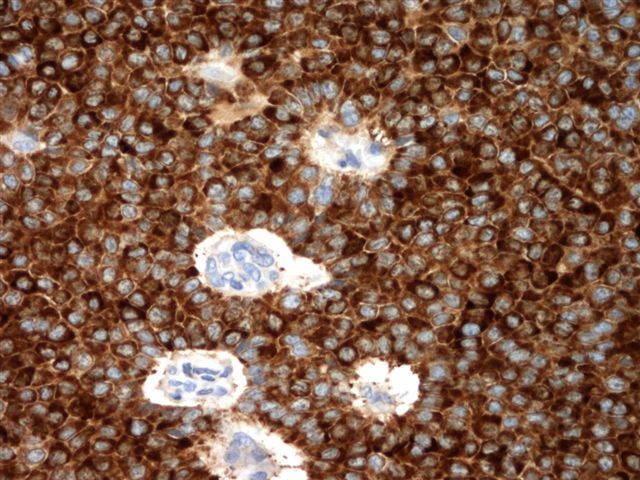

Microscopic (histologic) images

Contributed by Shabnam Zarei, M.D. and Sharon Bihlmeyer, M.D.

AFIP images

Positive stains

- FOXL2 immunostain is a sensitive (80%) and specific (99%) marker for sex cord stromal tumors (SCST), superior to α inhibin and calretinin and is positive in almost all SCST (98%) with FOXL2 mutation and a large number of those without mutation (67%); majority of adult GCTs (93%) are positive with FOXL2 stain and the immunostain cannot differentiate adult GCT from other SCSTs (Am J Surg Pathol 2011;35:484)

- SF1: most sensitive marker for this as well as most common sex cord stromal tumors (Am J Surg Pathol 2009;33:354)

- Inhibin A: more specific marker

- Calretinin (Am J Surg Pathol 2002;26:1477)